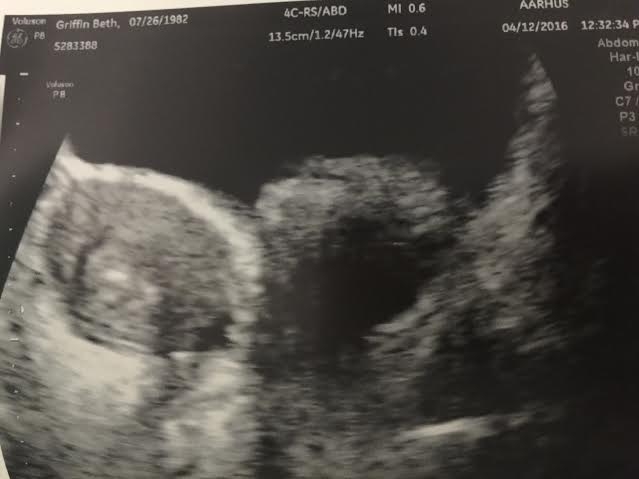

FET date: April 12, 2016 - DS born Dec 7, 2016

• Thanks ladies! Transfer went really well today. I love that DH got to be in the room. I went to acupuncture before and after the appointment so I'm feeling pretty relaxed. Just home taking it easy now. Let the TWW begin!